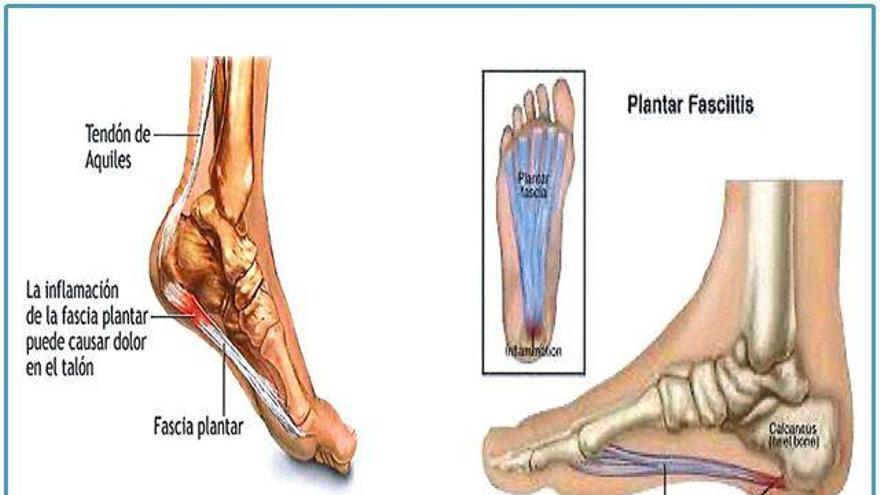

La fascitis plantar consiste en la inflamación de la fascia de la planta del pie. La fascia es un pequeño tejido fibroso, grueso y tenso que cubre los músculos que está formada por una estructura de tejido adiposo y conectivo que se sitúa en la planta del pie. Su función es amortiguar los impactos durante la carrera y estabilizar el talón.

La fascitis se identifica como un dolor en el talón o en la propia planta del pie y se siente especialmente al levantarte por la mañana.